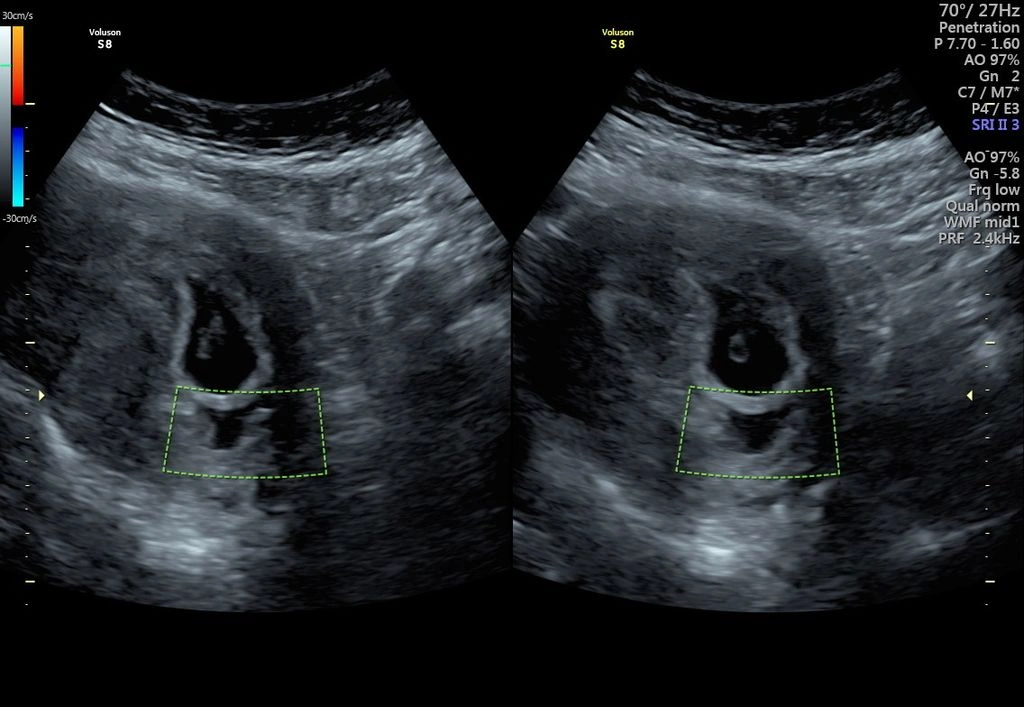

Thai 7 tuần siêu âm thấy gì

Khi siêu âm ở tuần thai thứ 7, bác sĩ thường có thể quan sát được:

- túi thai trong tử cung

- phôi thai rõ hơn

- túi noãn hoàng

- tim thai

Đây là thời điểm nhiều mẹ bầu lần đầu tiên được nhìn thấy và nghe tim thai của em bé.

Trong nhiều trường hợp, tim thai đã thấy rõ ở tuần thứ 7 khi siêu âm.